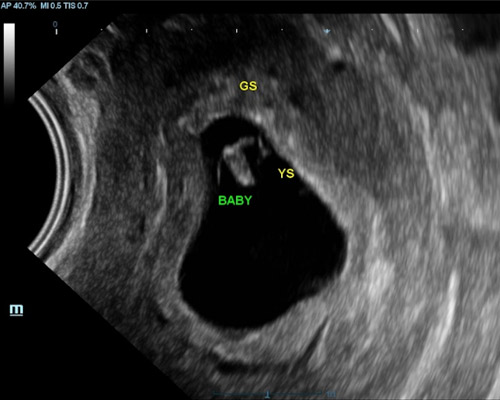

A viability scan is usually performed between 6 and 12 weeks to assess early development. It can help confirm the pregnancy, estimate dates, and check for key signs such as the gestational sac, fetal pole, and a heartbeat where visible. This scan is often chosen by those who want early clarity, have concerns, or simply wish for reassurance before their first routine appointment.

- Visual confirmation of the fetal heartbeat

- A 2D ultrasound to confirm an intrauterine pregnancy

Sometimes it may be needed to perform a Transvaginal (Internal) scan for clear imaging in addition to abdominal scan, this involves inserting a thin probe into the vagina. It is safe and your consent will be obtained beforehand.

The scan looks at early development, including location, measurements, and whether a heartbeat can be seen, depending on how far along you are.